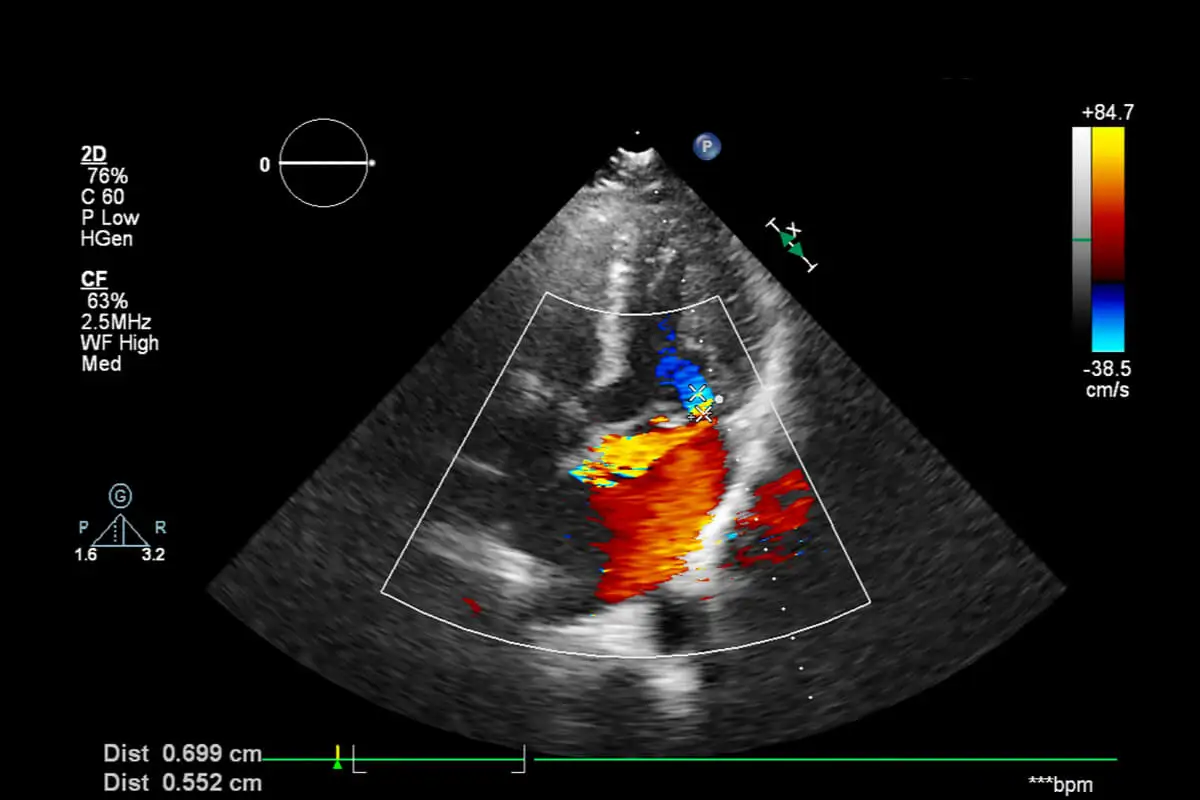

Flera uppföljande ultraljud rekommenderas. De utförs nästan alltid var 15:e dag för att övervaka utvecklingen. Dessutom ordinerar läkaren kompressionsstrumpor.